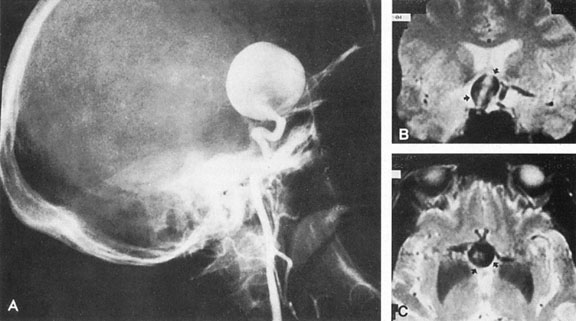

Intracavernous carotid aneurysms constitute only 2% to 3% of all intracranial aneurysms and are unique because of their location. These aneurysms arise from the internal carotid artery as it traverses the cavernous sinus4 (Fig. 3) and therefore produce a specific constellation of ocular and neurologic signs and symptoms. Rupture of such aneurysms, which are almost always saccular, may possibly result in carotid–cavernous sinus fistula, but subarachnoid hemorrhage is rare.5 However, slowly progressive enlargement is the rule, usually occurring within the cavernous sinus, with compression of the third, fourth, and sixth cranial nerves and later involving the first and second divisions of the fifth nerve (see Chapter 12).6 Progressive enlargement of the aneurysm forms a mass in the floor of the middle cranial fossa, compromising motor as well as sensory functions of the trigeminal nerve. Anterior expansion of the aneurysm erodes the anterior clinoid, optic foramen, and superior orbital fissure, eventually producing unilateral visual loss and exophthalmos. Posterior expansion, which occurs later, can erode the petrous portion of the temporal bone, causing ipsilateral facial palsy and, rarely, deafness. The sphenoidal sinus and the nasopharynx may infrequently be involved by inferior expansion and medial extension erodes into the sella and may simulate a pituitary tumor7 or cause bilateral ophthalmoplegia.8 Bilateral saccular intracavernous aneurysms occur uncommonly.9

Fig. 3. Magnetic resonance images of intracavernous aneurysm in a 72-year-old woman with left retrobulbar pain and sixth-nerve palsy. A: Coronal section (TR, 800 ms; TE, 30 ms). B: Parasagittal section (TR, 1000 ms; TE, 20 ms). C: Axial section (TR, 800 ms; TE, 30 ms). Note partial occlusion by thrombus (T). D: In a similar patient, carotid arteriogram (subtracted, lateral view) demonstrates a large intracavernous aneurysm.

Intracavernous aneurysms are suspected by the clinical presentation of a chronic cavernous sinus syndrome and are diagnosed by enhanced computed tomography (CT), magnetic resonance imaging (MRI), and arteriography (see Fig. 3). Because of the location and configuration within the cavernous sinus, direct surgical approaches to cavernous carotid aneurysms are hazardous. In recent years intravascular occlusion of the internal carotid by detachable balloon has evolved as a safe and successful procedure, often with relief of pain and improvement in ophthalmoplegia.10 Unfortunately, these balloons are commercially unavailable at the time of this writing.